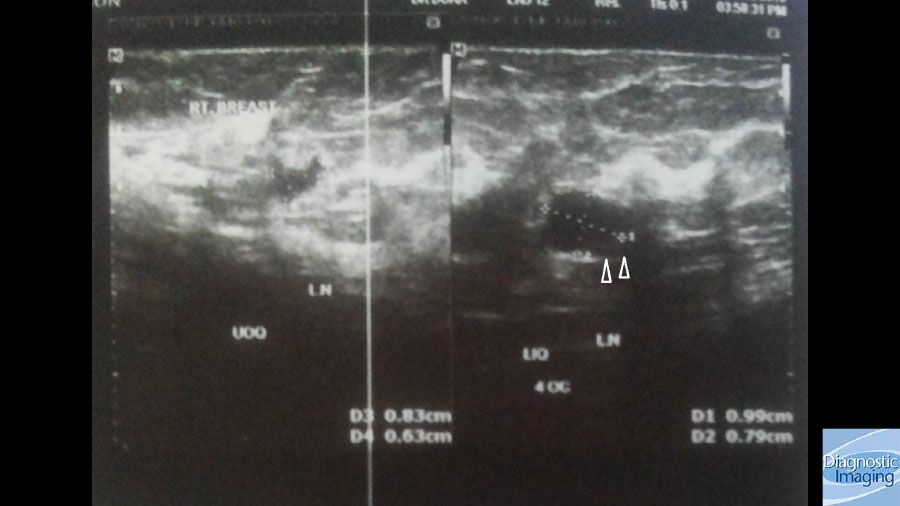

Case History: 49-year-old female presented with palpable right breast retroareolar mass.